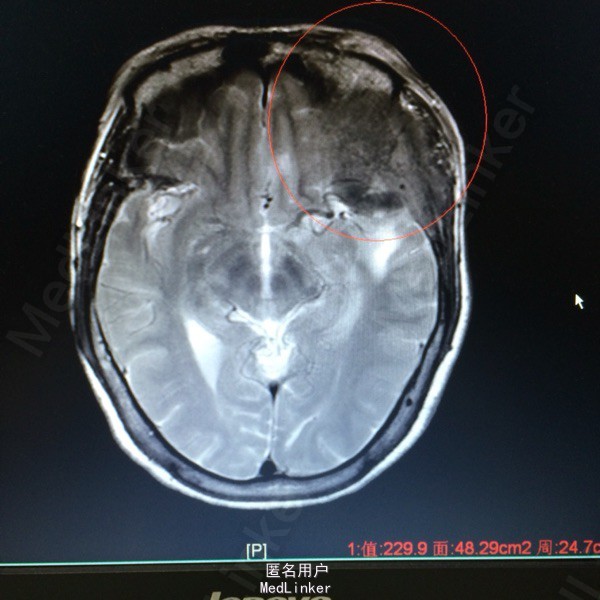

主诉:发现左侧额颞部包块2年余 病史:患者63岁女性,2年前无明显诱因出现左侧额颞部包块,无压痛等症状。1个月前开始出现左侧额颞部麻木不适,于外院查头颅MR提示:左侧额颞部占位。

查体:左侧额颞部可扪及一3*3大小隆起,无红肿,溃疡等。左侧眼球突出。 辅助检查,我院MR提示:左侧蝶骨大翼,额颞骨、中颅窝低,左眶顶璧、外侧璧骨质破坏,考虑恶性肿瘤的可能性较大。

诊断:左侧额叶非典型脑膜瘤 处理:行左额占位切除术➕颅骨重建术,病理提示非典型脑膜瘤